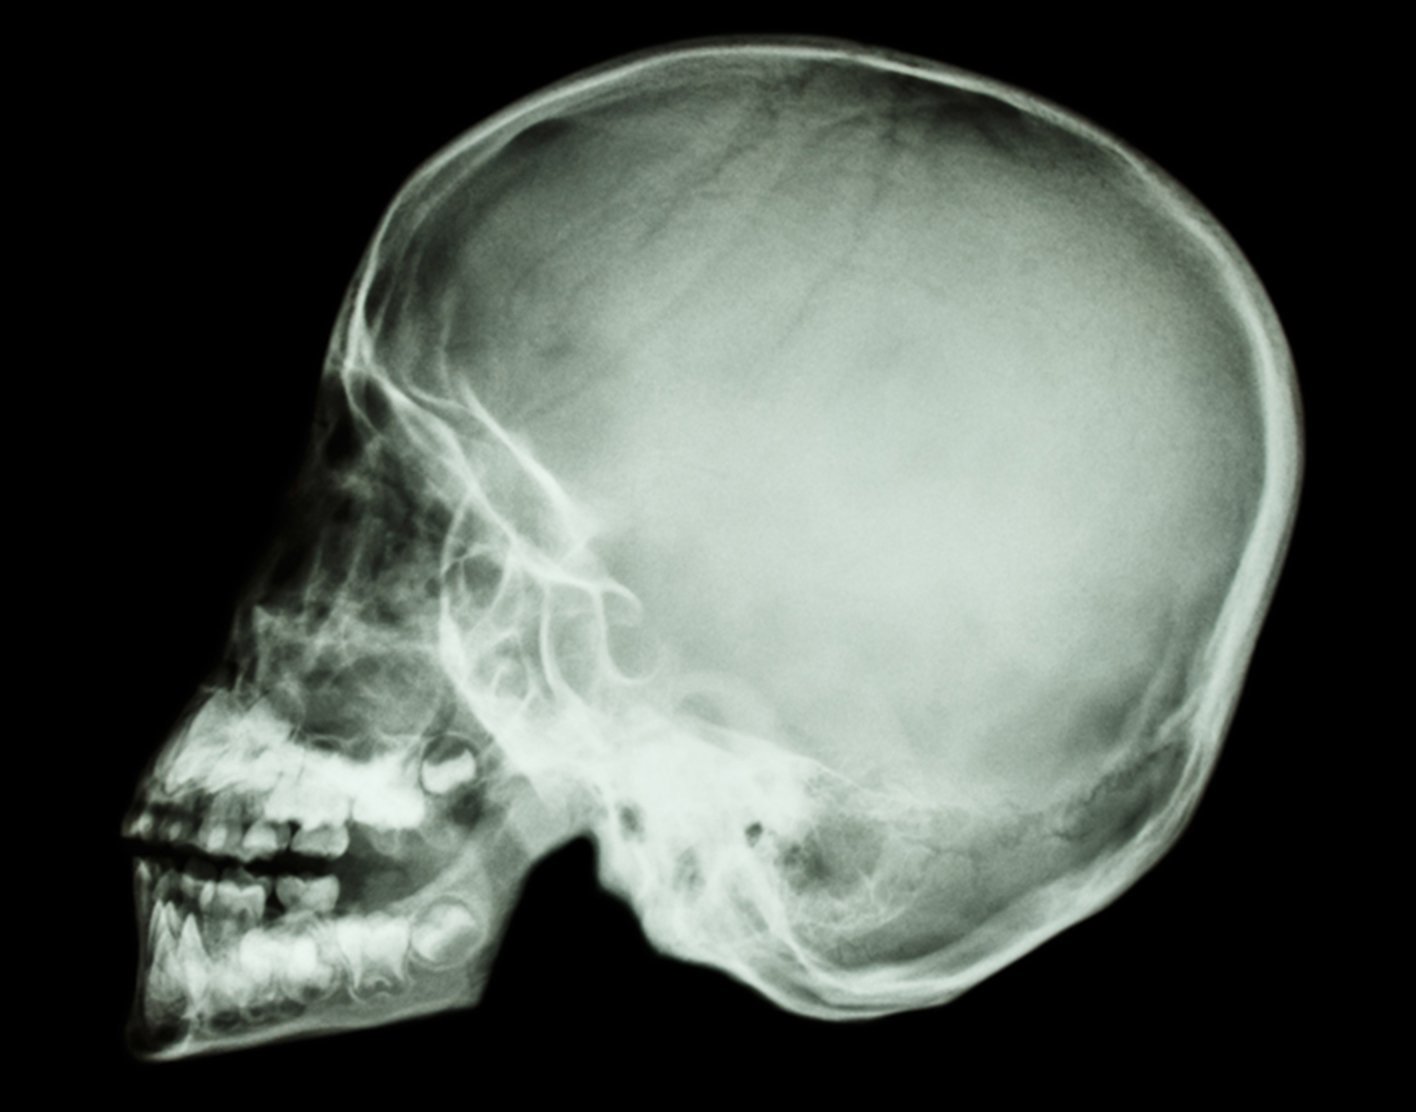

X-ray: x-rays, or “radiographs” use really high energy photons, that’s the same thing they were talking about when we’re talking about Light. Photons can be Red, photons can be Blue, photons can be really low power radio waves, and they can be really high power x-rays. When you take a really high power x-ray, which is a photon vibrating very very fast, with a higher frequency than even ultraviolet light, it can penetrate through the human body. Some of those x-rays will get absorbed on the way through, and others will not.

What determines whether they will go all the way through, and eventually hit a photographic plate on the other side?7 Well, if they hit something dense they’re more likely to be absorbed. If those photons hit something less dense, they cruise through. Bones are dense. Thus they are white on an x-ray because all those x-ray photons got absorbed and didn’t go through to the photographic plate on the back. When passing through the body containing muscle and blood vessels and brains and stuff, less of them get absorbed, and more of those photons hit a photographic plate. Like visual spectrum photons hitting a film negative, it gets darker. When we see x-ray radiographs, we’re looking at negatives, and unlike in photography, we don’t bother to flip the image so that white gets dark to the eye.

But that’s how we get an x-ray machine to make an x-ray picture. And then doctors can look at that and see what’s inside your body. We get the best resolution of bones — they’re the most dense.